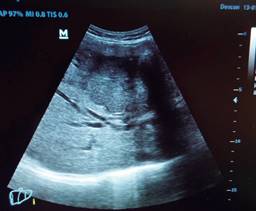

El cirujano general aborda particularmente problemas clínicos que incluyen el aparato digestivo, el cuello, la pared abdominal y los trastornos del sistema circulatorio y el tórax. Un artículo publicado en 2008, por Lindelius,15 demostró que la implementación del ultrasonido por parte del cirujano general en casos de dolor abdominal agudo incrementó en 7.9% la precisión diagnóstica. En la consulta cotidiana de la especialidad, incorporar el rastreo sonográfico al área explorada agrega minutos al examen clínico que aportan datos de notable valor por la objetividad y precisión. El abdomen suele ser el sitio que los cirujanos generales exploramos con más frecuencia. Es posible en una consulta cotidiana hacer todo el protocolo de ultrasonido de abdomen superior en minutos, que incluye ambos cuadrantes superiores y los flancos, pudiendo observar el hígado, la vesícula y los conductos biliares, ambos riñones, el bazo, parte del páncreas y, con ayuda del Doppler color, los principales vasos de la región como la vena cava inferior, la aorta abdominal, la vena porta, los vasos esplénicos y la arteria hepática. Puede haber limitantes como el contenido gástrico, el nivel de llenado de la vesícula biliar o la constitución del paciente y su capacidad de cooperar con el estudio. Pero con la práctica cotidiana, se adquieren las destrezas y el refinamiento suficientes para lograr, con la experiencia acumulada, producir imágenes de relevancia diagnostica inmediata. En la fase de entrenamiento, contrastar nuestros hallazgos con información disponible en la red, con los colegas imagenólogos, o cirujanos ya experimentados en ecografía, permitirá la retroalimentación y la tutoría esenciales de toda curva de aprendizaje. Tradicionalmente se consideraba que aquellos órganos que contienen una mezcla de líquido y gas (intestino, estómago) no son valorables por ultrasonido, el gas produce un efecto rarefacción, ya que no comprime las ondas como un tejido solido o un medio líquido, la señales entonces se dispersan impidiendo que regresen como ecos y permitan al procesador formar una imagen congruente con el órgano explorado. Sin embargo, cuando esta condición cambia como consecuencia de un estado patológico, es posible identificar el contenido intestinal o el gástrico y darnos una idea más aproximada de lo que realmente está ocurriendo en ese abdomen. Podemos, por ejemplo, saber si un estómago está lleno de líquido, o si el intestino contiene residuo sólido, líquido o gaseoso. Los equipos actuales pueden incluso ver en detalle la pared intestinal cuando ésta esté dilatada. Se puede distinguir cuando el colon está ocupado de líquido a nivel del flanco izquierdo como podría ser en una colitis amebiana o en una oclusión intestinal,16 donde se observa dilatación del intestino delgado ≥ 25 mm, el peristaltismo anormal, la presencia de líquido libre intraperitoneal y el edema de la pared intestinal (Figura 2). En casos de dolor abdominal agudo, el ultrasonido puede, en forma inmediata, permitir diagnósticos diferenciales como el hallazgo de una dilatación pielocalicial por nefrolitiasis (Figura 3), o un aneurisma de la aorta abdominal (Figura 4). Un estudio prospectivo realizado en Irvine, California,17 encontró que la a capacidad diagnóstica del médico de primer contacto practicando el ultrasonido para detectar una colelitiasis tiene una especificidad de 87% y una sensibilidad de 82%, mientras que la prueba de ultrasonografía realizada por radiología tuvo sensibilidad de 83% y una especificidad de 86%. Es decir, que, ahorrando tiempo al paciente, el diagnóstico de colelitiasis es factible agregando unos minutos al examen físico inicial. En casos de apendicitis, el método diagnostico considerado como el estándar de oro es la tomografía axial computarizada (TAC). Sin embargo, tiene inconvenientes como su disponibilidad, su costo, el riesgo de radiación en niños y pacientes embarazadas. En tales situaciones, sobre todo en niños, sexo femenino o pacientes delgados, el ultrasonido es una poderosa herramienta que complementa el examen clínico inicial. Las ventajas del ultrasonido frente a la tomografía serian su ubicuidad (ya está en la sala de emergencias), el bajo costo, la ausencia de radiación y el diagnóstico diferencial con causas ginecológicas o genitourinarias de dolor. En apendicitis, la sensibilidad y especificidad de la TAC es de 99.4% y 80.0%, respectivamente. Para el ultrasonido, la sensibilidad diagnóstica es de 83% y la especificidad de 90%. La tasa de apendicectomía negativa es ligeramente mayor en el grupo de TAC que en el del ultrasonido, es decir, 7.1% (3/42) (TAC) en comparación con 4.67% (5/107) (ultrasonido). Hay que recalcar que el ultrasonido es operador dependiente. La experiencia y la calidad del equipo juegan un papel importante.18 La apendicitis tiene varios hallazgos característicos, como la pared edematosa y el aumento de grosor general. Se toman para criterios de positividad una estructura tubular aperistáltica no compresible que mide más de 6 mm de diámetro en el cuadrante inferior derecho (Figura 5).19-21

Figura 4: Aneurisma abdominal. Hallazgo incidental en la consulta de un paciente que acude por un cuadro de dolor abdominal por herpes zóster.